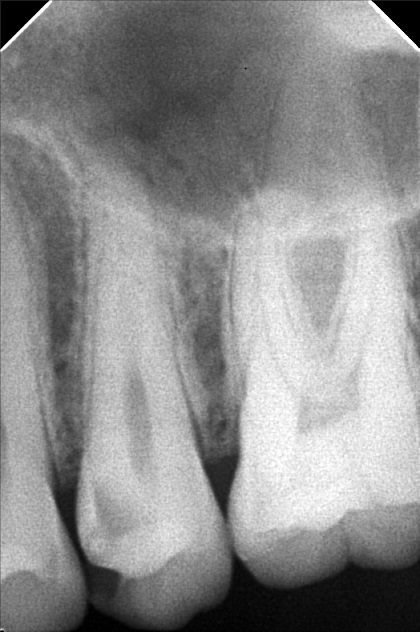

- Procedure

- ma-_zorina_cabas_03.jpg